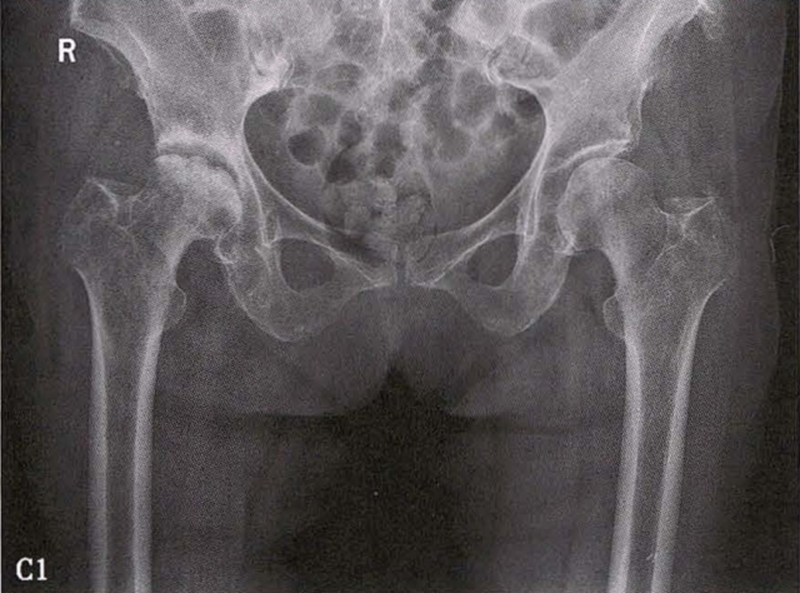

C.女性,89岁,右侧股骨头坏死Ⅳ期。X线片示右侧股骨头压缩变扁,右侧髂臼密度增高,关节内侧间隙狭窄、不均匀(C1)。MRI示右股骨头压缩变扁,右髋关节腔比较多积液(C2)。